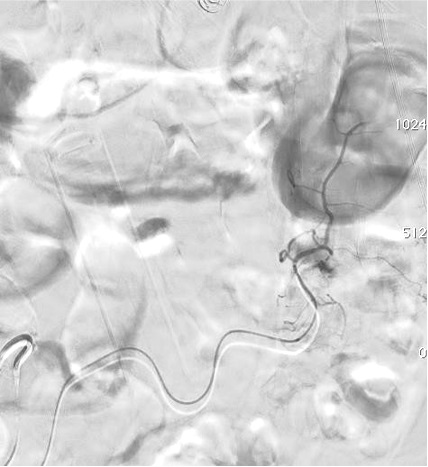

病例二 Onyx

病例三:Front and back door  embolization with  Onyx

病例四:Also possible with Glubran2  (< 4 vasa recta)